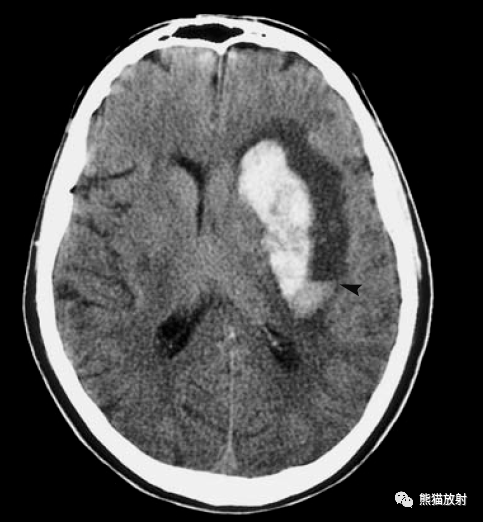

61a皮质动脉的穿通支-------脑叶出血61b豆纹动脉

脑实质内出血丨演变,分布,ct表现